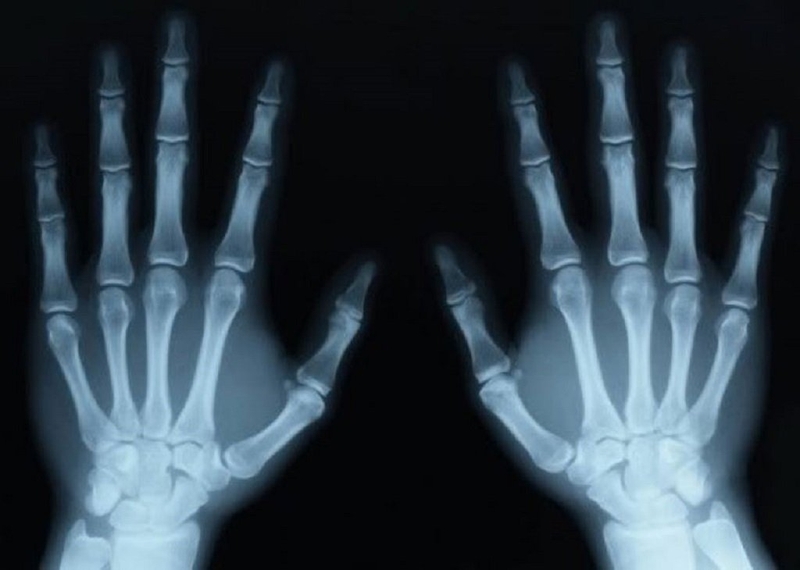

Phương pháp xác định tuổi xương là kỹ thuật đánh giá sự trưởng thành của trẻ em và thanh thiếu niên mà không cần phải dựa vào độ tuổi họ. Quy trình đo tuổi xương thường bao gồm việc sử dụng phim chụp X-quang của xương tay hoặc chân, sau đó so sánh với các thước đo chuẩn trong bảng tham chiếu. Bài viết dưới đây của Nhà thuốc Long Châu sẽ chia sẻ tới bạn đọc những điều cần biết về tuổi xương và các bước xác định tuổi xương.

Về cách xác định tuổi xương thì hiện nay với sự tiến bộ của y học và sự hỗ trợ của các thiết bị hiện đại, quá trình này đã trở nên dễ dàng hơn. Bác sĩ thường áp dụng kỹ thuật chụp X-quang để thu thập hình ảnh và ước lượng tuổi xương của trẻ. Sự ứng dụng công nghệ chụp X-quang giúp đảm bảo độ chính xác tương đối cao trong quá trình chẩn đoán.

Trong thực tế, quy trình xác định tuổi xương cho trẻ nhỏ thường bao gồm ba bước chính. Đầu tiên sẽ sử dụng kỹ thuật chẩn đoán hình ảnh tia X-quang để chụp bàn tay và chân bên trái của trẻ. Dựa vào hình ảnh thu được, bác sĩ so sánh với bảng Atlas để từ đó xác định tuổi xương. Quy trình này đơn giản với những kỹ thuật hiện đại, không tạo ra tình trạng sợ hãi hay ảnh hưởng đến sức khỏe của trẻ, mang lại sự an tâm cho các bậc phụ huynh khi đưa con đi kiểm tra tuổi xương.

Để đảm bảo độ chính xác, bác sĩ còn đưa ra một số lưu ý khi chụp hình X-quang bàn tay và chân. Cần chú ý đến hình dạng của đốt xương ngón tay, kiểm tra kích thước của các điểm cốt hóa quan trọng trong xương cổ tay của trẻ. Đồng thời, quan trọng nhất là không bỏ qua việc kiểm tra tình trạng liền điểm cốt hóa tại xương quay.